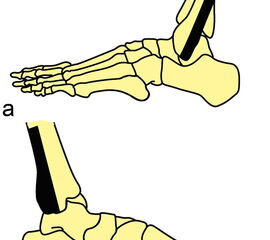

Die klinische Untersuchung nimmt einen hohen Stellenwert ein. Um zuverlässig zwischen einer Distorsion und einer Fraktur zu differenzieren, d.h., um zu entscheiden, ob eine Röntgen-Untersuchung des Sprunggelenkes notwendig ist, kann die „Ottawa Ankle Rule“ angewendet werden. Dabei erfolgt die Untersuchung definierter Druckpunkte (Abbildung 1). Ist einer dieser Punkte druckschmerzhaft oder die Gehfähigkeit > 4 Schritte eingeschränkt, ist eine Röntgendiagnostik zum Ausschluss einer Fraktur indiziert. Das Risiko, eine Fraktur unter Anwendung dieser Regel zu übersehen, liegt bei lediglich 0,4% 34. Auch die klinische Testung der Syndesmose (Syndesmosenschmerz und Schmerzen bei Außenrotation – (Abbildung 2) hat eine hohe Sensitivität für Frakturen und Syndesmosenverletzungen 5 (Level 2b Empfehlung der aktuellen S2-Leitlinie zur Sprunggelenksfraktur).